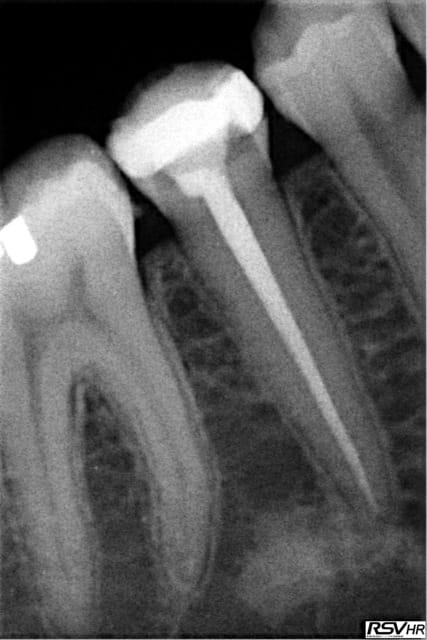

pourquoi l'endo au fait (nécrose racine distale de 46)

préparation Mtwo et j'aime bien .

allez une dernière sympa et pi après j'arrête mais la technique est reproductible .

Ton obtu c'est à chaud n'est-ce pas ?

pour te répondre je ne pense pas je travaille avec binocculaire (ebay d'accord) mais pas trouvé et de plus si tu regardes bien on a la même impression avec la racine distale vraisemblablement artefact.

pas du tout : maître cône adapté scellé "à froid" on pourrait comparer ma méthode d'obturation à lentulo + cone que j'utilise sans honte ...